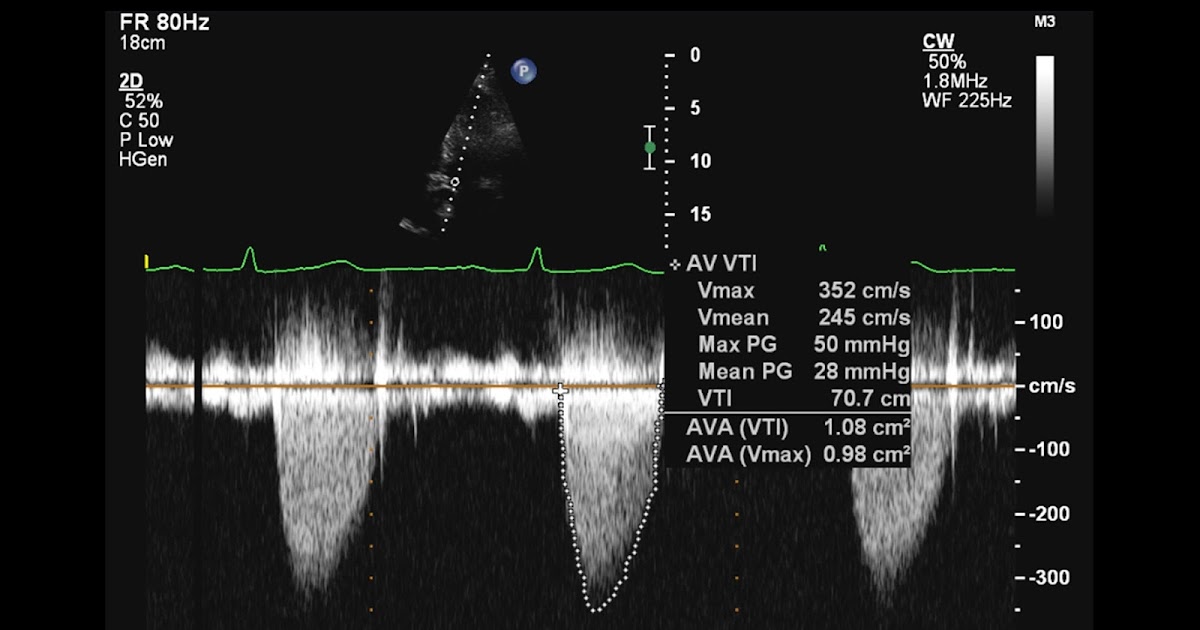

From arhcardio.blogspot.com

Andrew R. Houghton What's the best probe position to assess aortic What Is Probe Assessment probe running record. here you will be able to learn how to conduct a probe reading assessment. probe reading comprehension assessment (probe) is an assessment resource that can help make these observations. although the probe reading assessment is widely used to assess the reading comprehension of students in new. Assessing reading skills, specifically comprehension, is difficult.. What Is Probe Assessment.